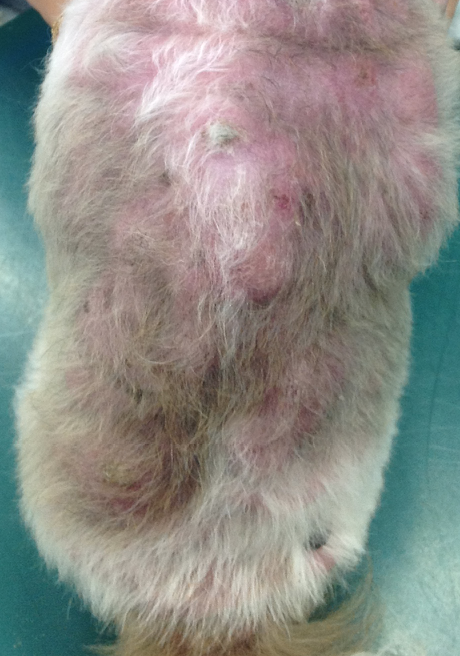

劇症膵炎による膵壊死、化膿性腹膜炎を呈した猫。

ねこちゃんの膵炎のなかでも急性に発病して重症化しやすい病気です。

case.1

雑種猫、6歳齢、去勢雄

predonisolone、ampicilline、enrofloxacin、nafamostat、maropitant、metoclopramide CRI、静脈輸液、経鼻チューブフィーディングにより急性期治療実施。